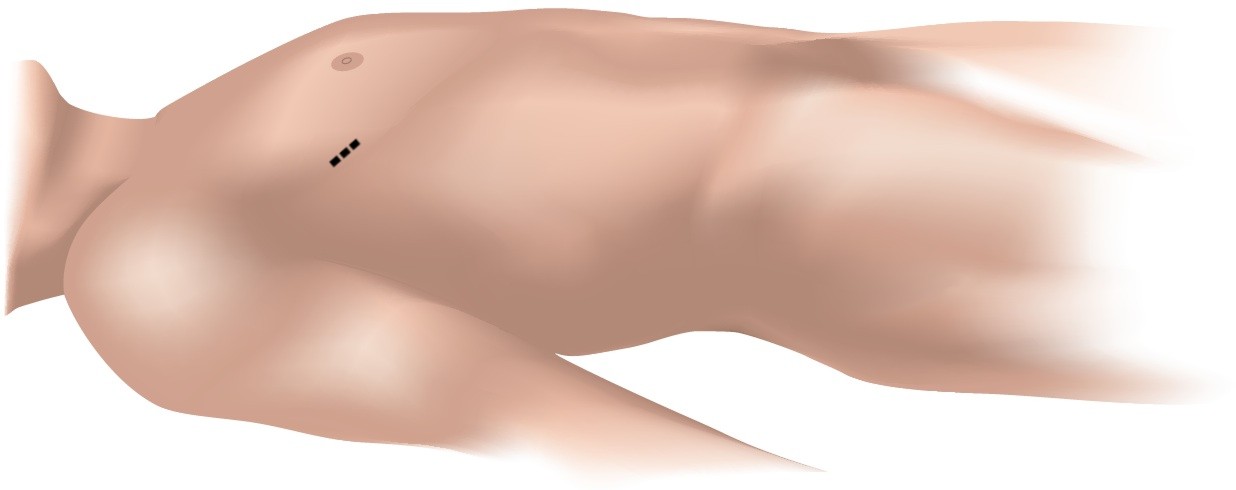

Most patients with an ASD are candidates for minimally invasive surgery. Surgeons perform the operation by making only a small 4-6 cm incision on the right side of the chest instead of the large midline-incision and division of the sternum used in traditional open surgery.

Fig. 3 - Incision